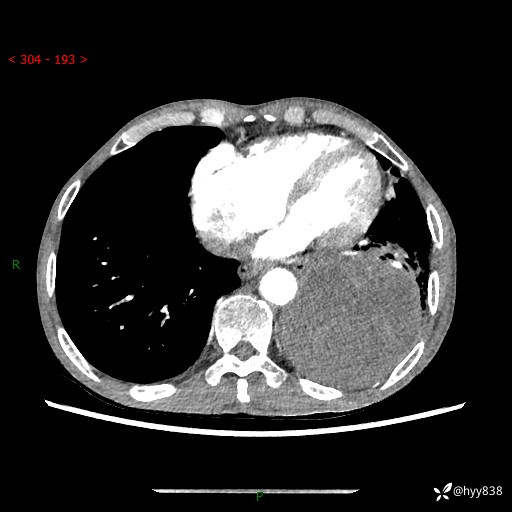

77岁/男,腹痛2月,CT发现左肺占位1天。巨大肿块,肺内或肺外来源…结果公布~

主诉:腹痛2月,CT发现左肺占位1天

现病史:患者于2025年9月间断左下腹胀痛,在当地镇卫生院行彩超检查考虑泌尿系结石,行止痛排石对症治疗未见明显好转;1天前腹痛症状加重,至当地市第三人民医院行CT检查:左肺下叶巨大团块状软组织影,考虑肿瘤性病变,建议增强CT检查;左侧胸腔积液;纵膈内淋巴结肿大;双肺肺气肿;右肺中叶纤维灶。为进一步求治,来我院就诊。

胸部CT平扫+增强